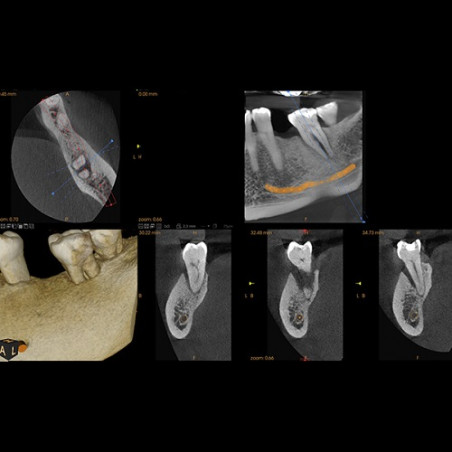

Tomografía

El nuevo standard de diagnóstico

La tomografía dental, también conocida como tomografía computarizada dental o tomografía cone beam (CBCT), es una técnica de diagnóstico por imágenes que proporciona imágenes tridimensionales detalladas de las estructuras dentales y maxilofaciales. A diferencia de las radiografías dentales convencionales, la tomografía dental permite a los profesionales de la salud dental visualizar las estructuras en 3D, lo que resulta especialmente útil en situaciones donde se requiere una evaluación más completa.

- La tomografía cone beam utiliza un haz cónico de radiación para obtener imágenes tridimensionales de los dientes, los maxilares, la mandíbula y las estructuras circundantes.

- La tomografía dental se utiliza en una variedad de situaciones, como la planificación de implantes dentales, la evaluación de las vías respiratorias superiores, la detección de quistes o tumores, el diagnóstico de fracturas, y la visualización de las estructuras anatómicas antes de procedimientos quirúrgicos.

Imágenes 3D Detalladas: Proporciona imágenes tridimensionales detalladas que permiten una visualización más completa de las estructuras.

Mejora la Planificación de Tratamiento: Facilita la planificación precisa de procedimientos dentales, como la colocación de implantes o extracciones.

- Además de la planificación de implantes, se utiliza en ortodoncia para evaluar el crecimiento facial y en endodoncia para evaluar estructuras radiculares.